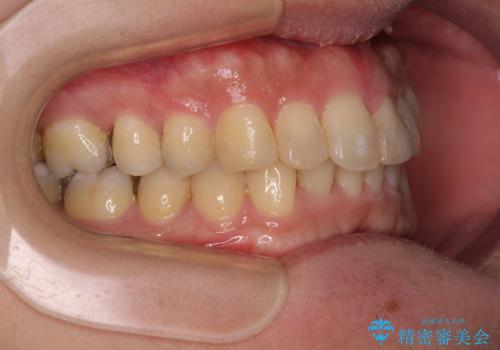

- 深い咬み合わせによる食いしばりで、顎関節や頭が痛むことがあるとのことで来院された患者様です。

歯ぎしりができないくらい強い食いしばりの咬合状態であったため、奥歯の歯軸を起き上がらせることで咬合を挙上させ、歯ぎしりができるようにしていくこととしました。

下顎が左側にずれているため、上下正中は最大限合わせられるところまで合わせるゴールとなりました。